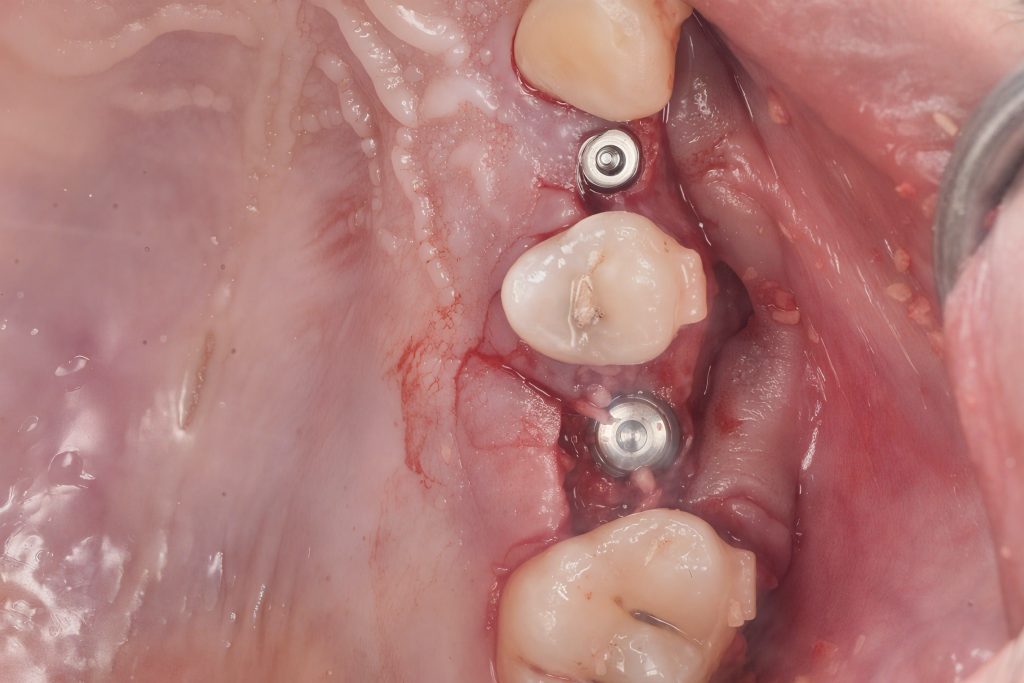

Under local anesthesia, a full-thickness mucoperiosteal flap was raised. Sequential osteotomy drills were performed up to 1 mm short of the sinus floor. Osteotomes of increasing diameters were used to carefully fracture the sinus floor through controlled malleting, lifting the Schneiderian membrane atraumatically (Fig 2).